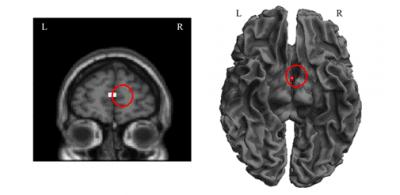

Brain activation when processing Chinese hand-radicals

A number of studies in which patients with lesions to frontal pre-motor areas are included have identified deficits in action comprehension. In addition, imaging studies have revealed the activation of brain areas associated with perception or action during tasks involving reading of words with related semantic meaning. For example, the mere passive reading of action verbs such as kick, pick and lick has been found to activate areas of the sensory-motor cortex associated with the legs, hands and face, respectively. To investigate the semantic processing of Chinese radicals and Chinese characters, Qing-Lin Wu and team from Taiwan Normal University divided 72 high-frequency Chinese characters into four categories: hand-action verbs with and without hand-radicals, and verbs not related to hand actions, with and without hand-radicals. Twenty-eight healthy participants, aged 21-30 years, underwent functional MRI scans while reading the characters. Compared to characters without hand-radicals, reading characters with hand-radicals activated the right medial frontal gyrus. The findings may be consistent with embodied semantics theory and suggest that neural representation of radicals is indispensable in processing Chinese characters. This study by the research team of Qing-Lin Wu, published in the Neural Regeneration Research (Vol. 8, No. 20, 2013), enhances our understanding of the neural substrates underlying the process of reading in Chinese, with potential benefits for the development of treatments for dyslexia.

Article: " Processing Chinese hand-radicals activates the medial frontal gyrus: a functional MRI investigation," by Qing-Lin Wu1, Yu-Chen Chan2, Joseph P. Lavallee3, Hsueh-Chin Chen4, Kuo-En Chang5, Yao-Ting Sung4 (1 Department of Educational Psychology and Counseling, Taiwan Normal University, Taipei, Taiwan, China; 2 Institute of Learning Sciences, Tsing Hua University, Hsinchu, Taiwan, China; 3 School of Education and Applied Linguistics, Ming Chuan University, Taipei, Taiwan, China; 4 Department of Educational Psychology and Counseling, Taiwan Normal University, Taipei, Taiwan, China; 5 Graduate Institute of Information and Computer Education, Taiwan Normal University, Taipei, Taiwan, China)